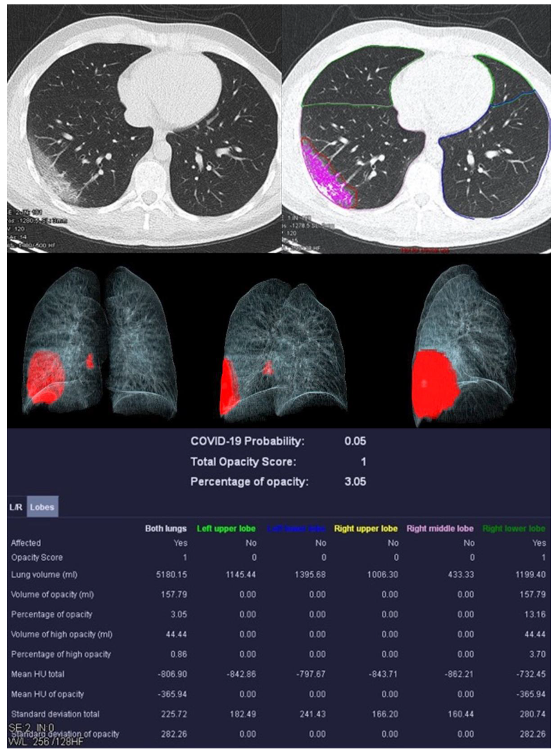

| Mean COVID-19 Probability ± SD | 0.80 ± 0.36 | 0.33 ± 0.4 | 0.55 ± 0.47 | 0.66 ± 0.44 |

| Mean LSS ± SD | 8 ± 5 | 5 ± 4 | 5 ± 6 | 0 ± 0 |

| Mean PO ± SD in % | 26.39 ± 23.22 | 12.52 ± 17.97 | 18.90 ± 26.27 | 0.05 ± 0.12 |

| Mean PHO ± SD in % | 6.42 ± 7.68 | 3.60 ± 4.47 | 5.86 ± 10.04 | 0.01 ± 0.02 |

| Mean HU total | −679.57 ± 112.72 | −750.12 ± 84.05 | −715.10 ± 37.28 | −820.18 ± 36.45 |

| Mean HU of opacity | −453.40 ± 170.46 | −427.39 ± 157.92 | −450.47 ± 115.38 | −416.18 ± 298.62 |